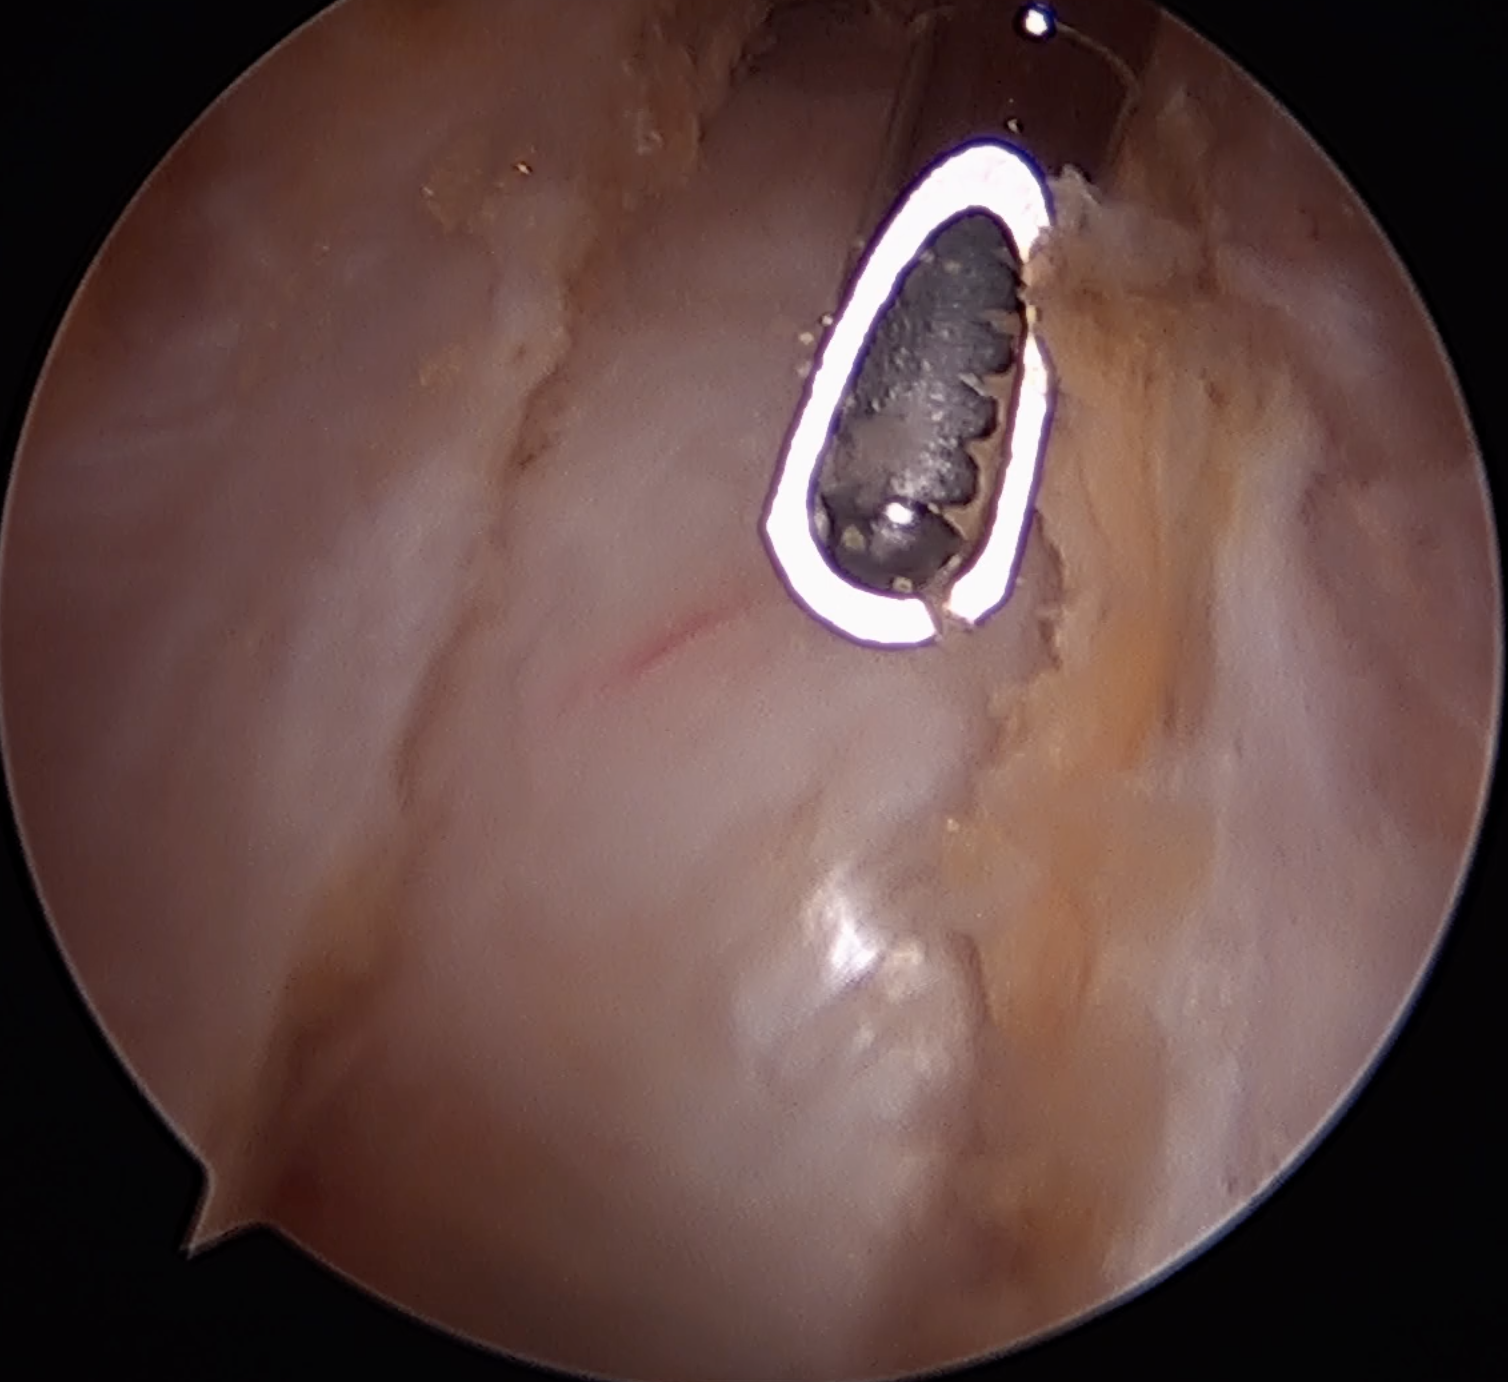

ITB vertical split / cruciform release + trochanteric bursectomy

Arthroscopic technique article

ITB band Longitudinal split

Cruciform release anteriorly Bursectomy over abductors